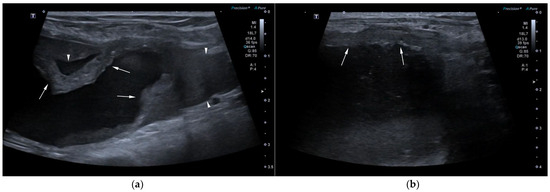

Uterus masculinus is a rare disorder of sexual development in males, characterized by the presence of tubular female genitalia. Diagnostic imaging reports of infected uterus masculinus are limited. We describe the ultrasonographic and computed tomographic findings in three dogs, all presenting with abdominal distension, pain, and systemic infection. Imaging consistently revealed a fluid-filled, bicornuate structure arising from the prostate. In two dogs, the horns extended through the inguinal rings to the scrotal testes; in the third, with a prior left orchiectomy, both horns were intra-abdominal, the right ending in a peritoneal mass. Surgery and histopathology confirmed infected uterus masculinus, with Escherichia coli isolated from urine in all dogs and from the structure in two. Two dogs had Leydig cell tumors, one with concurrent uterine neoplasia; the third had an ovarian or ovotesticular granulosa cell tumor. Although rare, infected uterus masculinus is potentially life-threatening and should be considered in male dogs with abdominal pain, distension, or systemic infection. This is the first case series describing combined ultrasonographic and tomographic features of infected uterus masculinus, including novel findings such as cervix-like mural narrowing and fluid–fluid levels. It is also the first imaging description of an ovarian or ovotesticular tumor in a dog with uterus masculinus. Full article

Figure 1